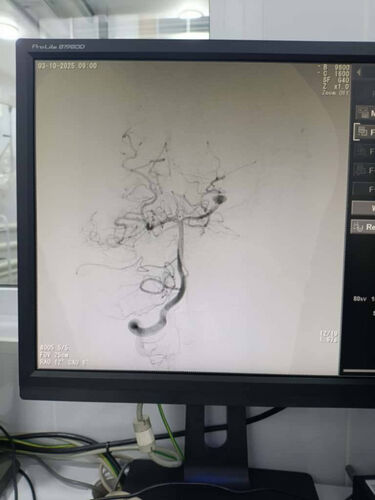

Нейрохирурги Национального центра охраны материнства и детства совместно с коллегами из Национального госпиталя провели несколько высокотехнологичных эндоваскулярных операций детям с тяжелыми сосудистыми заболеваниями головного мозга - аневризмами и артериовенозными мальформациями.

Отмечается, что операции проходили в современной ангиографической операционной с применением новейших методов интраоперационной визуализации. В составе команды работали эндоваскулярные нейрохирурги, анестезиологи-реаниматологи, рентген-лаборанты и специалисты по интенсивной терапии. Такой подход обеспечил высокий уровень безопасности, точность диагностики и эффективность лечения.

На дооперационном этапе выполнялась ангиографическая диагностика, позволившая определить размеры и расположение сосудистых аномалий и выбрать оптимальную эндоваскулярную тактику для каждого пациента.

При лечении аневризм выполнялась эндоваскулярная окклюзия с сохранением проходимости магистральных сосудов, а при артериовенозных мальформациях - точечная эмболизация патологического узла для предотвращения риска кровоизлияния. Все манипуляции осуществлялись под контролем цифровой субтракционной ангиографии.

После операций проведена контрольная ангиографическая оценка, подтвердившая успешное выключение патологических очагов из кровотока и отсутствие осложнений. Все дети благополучно вышли из наркоза и переведены в отделение реанимации для наблюдения. По данным врачей, состояние пациентов стабильное, осложнений не отмечено, восстановление проходит активно.